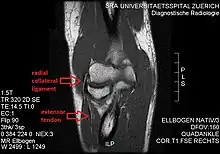

| Radial collateral ligament | |

![]() Left elbow joint, showing posterior and radial collateral ligaments. (Radial collateral ligament visible near center.) | |